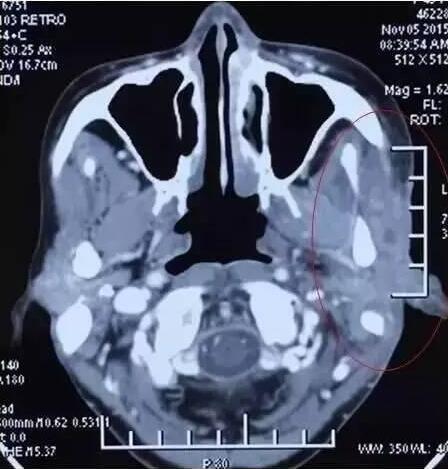

腮腺癌

患者女性,63岁。

A45治疗前

A45治疗一个疗程后,病灶缩小非常明显,皮肤逐渐愈合好转。